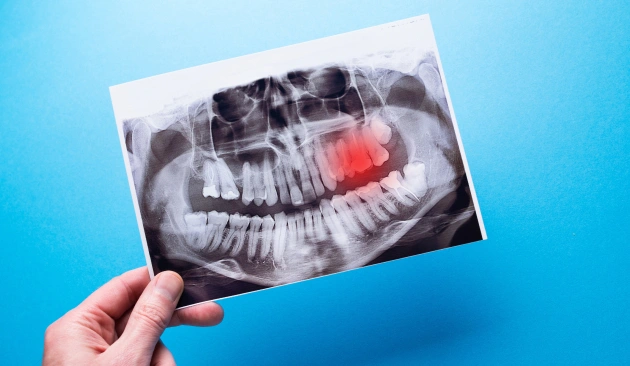

Cysts or decay detected on X-ray

Digital X-rays and advanced diagnostic tools help map the tooth’s position, nerves, and bone structure, ensuring accurate planning and minimal post-operative discomfort.

Full evaluation and X-ray to plan your tooth removal safely.